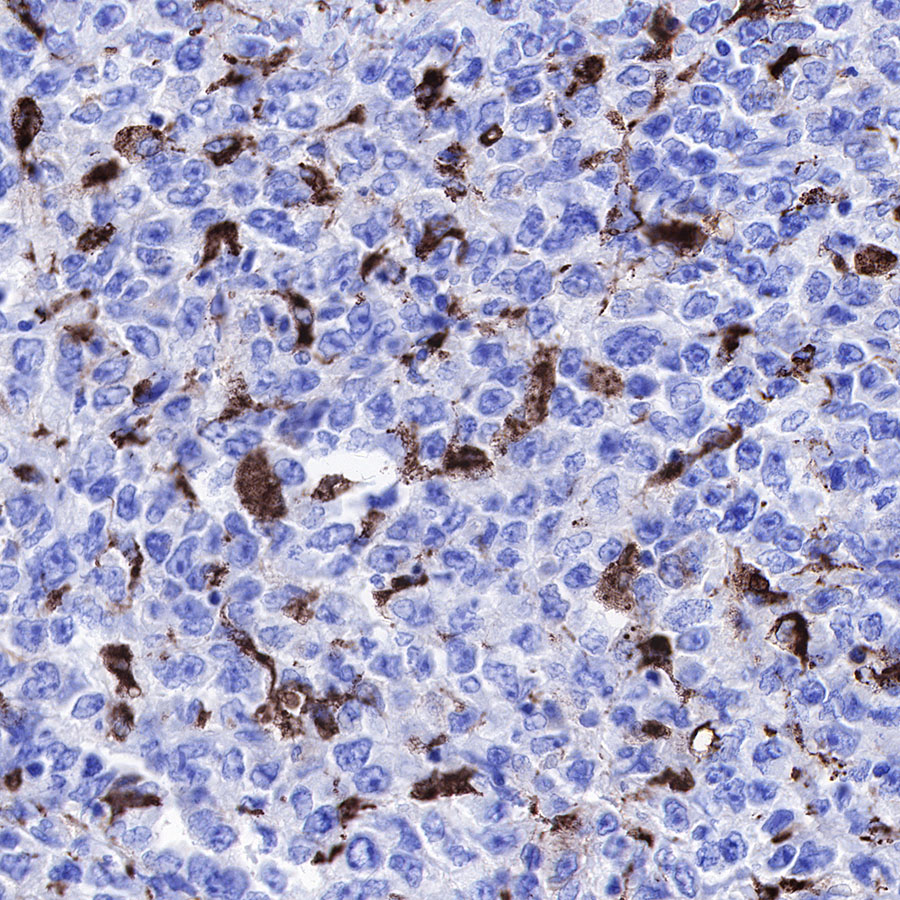

IHC shows positive staining in paraffin-embedded human diffuse large B-cell lymphoma. Anti-CD68 antibody was used at 1/1000 dilution, followed by a HRP Polymer for Mouse & Rabbit IgG (ready to use). Counterstained with hematoxylin. Heat mediated antigen retrieval with Tris/EDTA buffer pH9.0 was performed before commencing with IHC staining protocol.